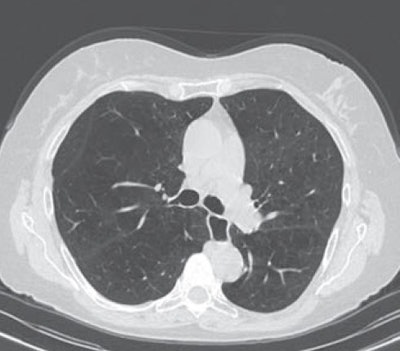

A 65-year-old man with severe lung emphysema (light blue on images below) seen on axial CT image (image 1 above), CT image including AI-based calculation (image 2), and 3D model (image 3). Extent of low-attenuation volume is seen inside green outline in both lungs in image 2. Purple outline in anterior right part of image 2 marks boundary between upper and middle lobes. Gray outline in image 2 correctly segments lower part of upper lobe and ensures that all lung tissue was considered. Also in image 2, orange outline denotes margin of tracheobronchial tree, and blue outline denotes margin of left lower lobe. All images courtesy of the AJR.Those results indicate that AI-based emphysema quantification meaningfully reflects clinical pulmonary physiology, according to the researchers.